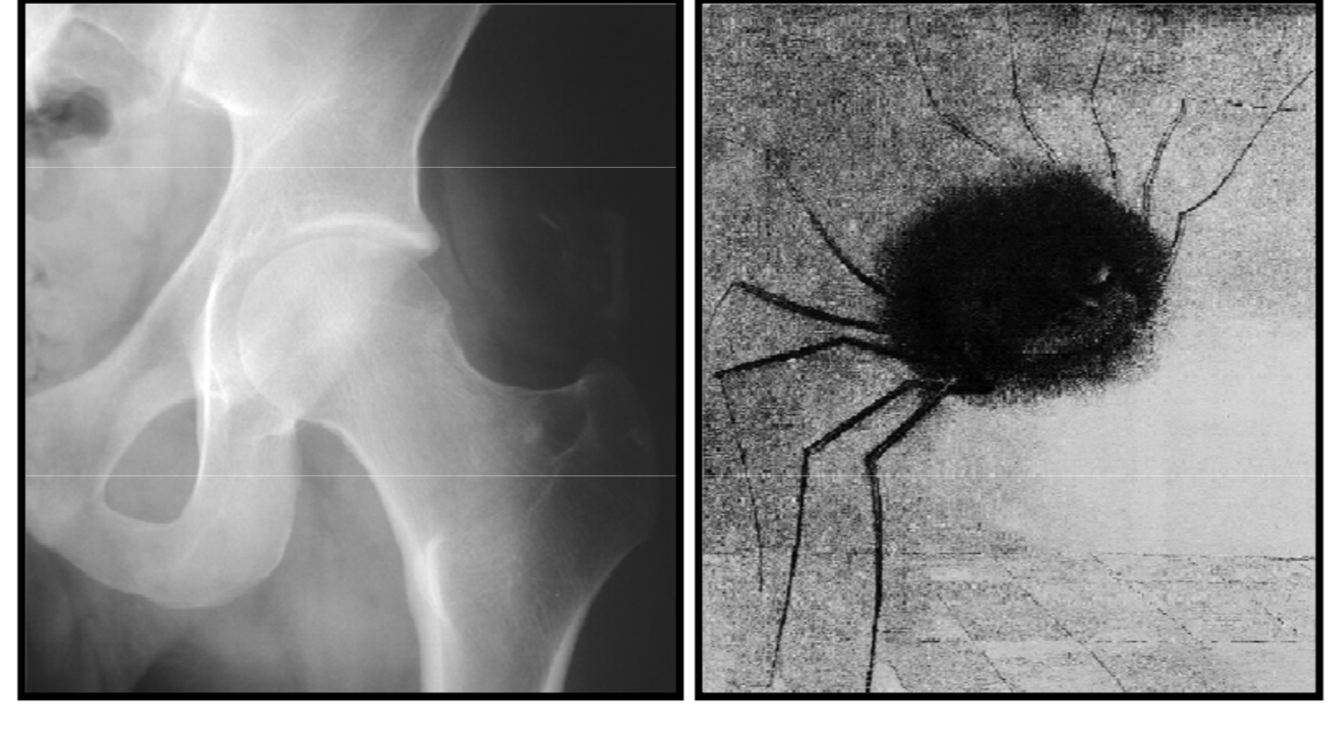

Synovial herniation pit or Pitt’s pit

variation anat normal